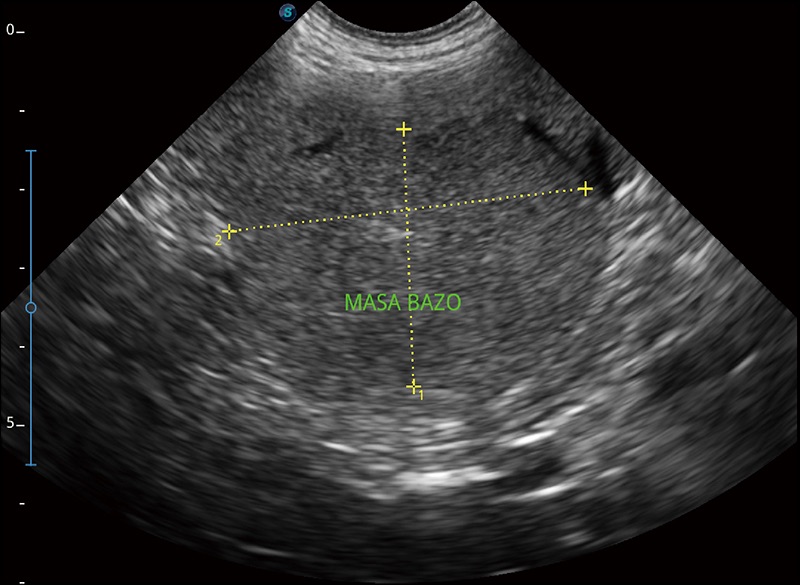

临床图